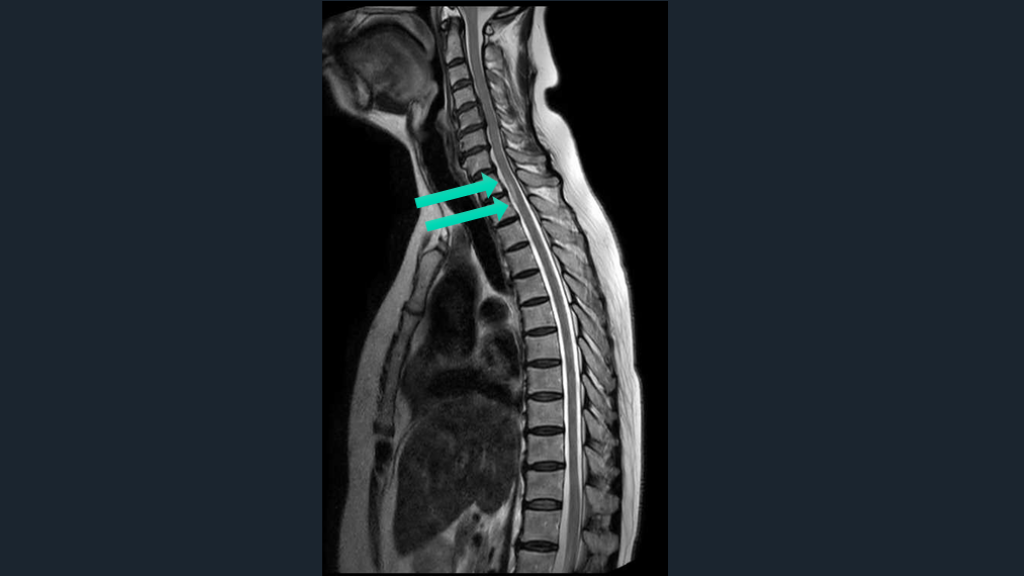

脊髄障害は、 悩むならwhole spine MRI 矢状断をとっておく。 TIPS

#53.

CASE 70歳女性例。突発発症の下肢対麻痺である。 先ほどのアイデアのごとく、4つの鑑別をまずは挙げる。 そして、MRIではどこを撮るのか?は正直、難しい。 正直、かっこつけずに、whole spine MRIでよいと思う。

#57.

脊髄障害の初手はwhole spineでよい。 脊髄緊急疾患でのWhole spine-MRIは推奨。 ER脊髄障害S/Oで、約半数の症例の脊髄緊急疾患診断に有用だった。 特に、外傷、麻痺、および排便/排尿症状患者で価値ある可能性 解説 Curr Probl Diagn Radiol. 2021;50:637-645. Handb Clin Neurol. 2017:140:319-335.

#58.

脊髄障害の初手はwhole spineでよい。 脊髄障害の高位診断は正直難しい。 症状の高位と実際の脊髄障害の高位は異なる。 実際の障害高位は、症状の高位よりも、より上にある。 対麻痺なら、腰髄レベルよりもより高位でどこでもあり。 腰髄レベルMRIのみ施行なら空振りリスクある。 それなら、WS-MRIの撮影でもよかろう。 解説

#59.